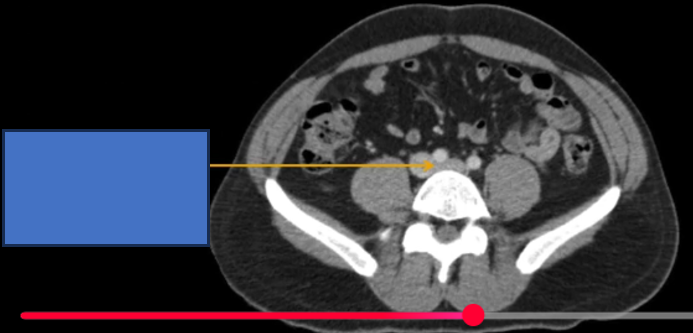

cq trong hình ?